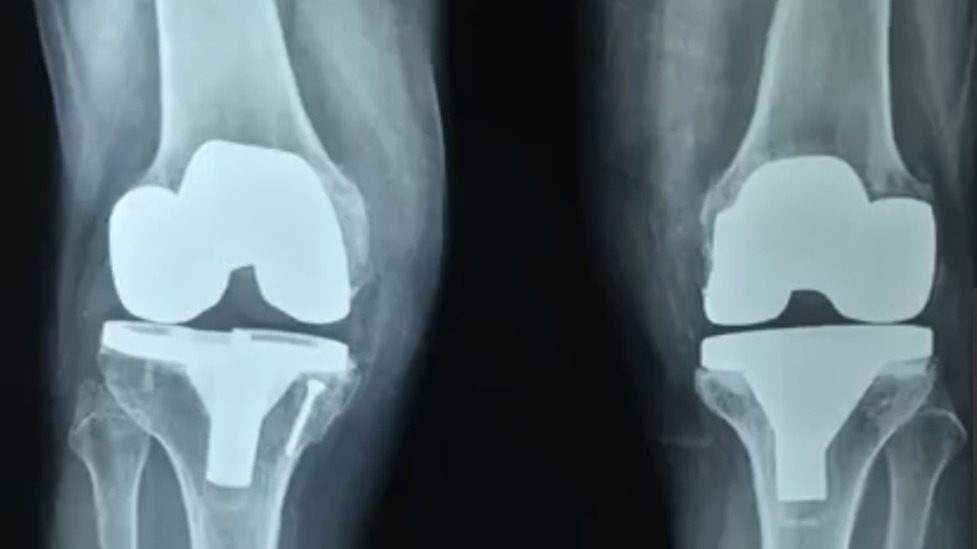

total knee replacement of 58 year old woman

This is one of my early IPGMER days total knee replacement (tkr) surgery done on the right knee for grade 4 osteoarthrosis with medial tibial deficiency that was counteracted with bone graft held with screws. This post would be incomplete without gratitude to Dr. Debasis Mukherjee and Dr. @Chetan Chetan